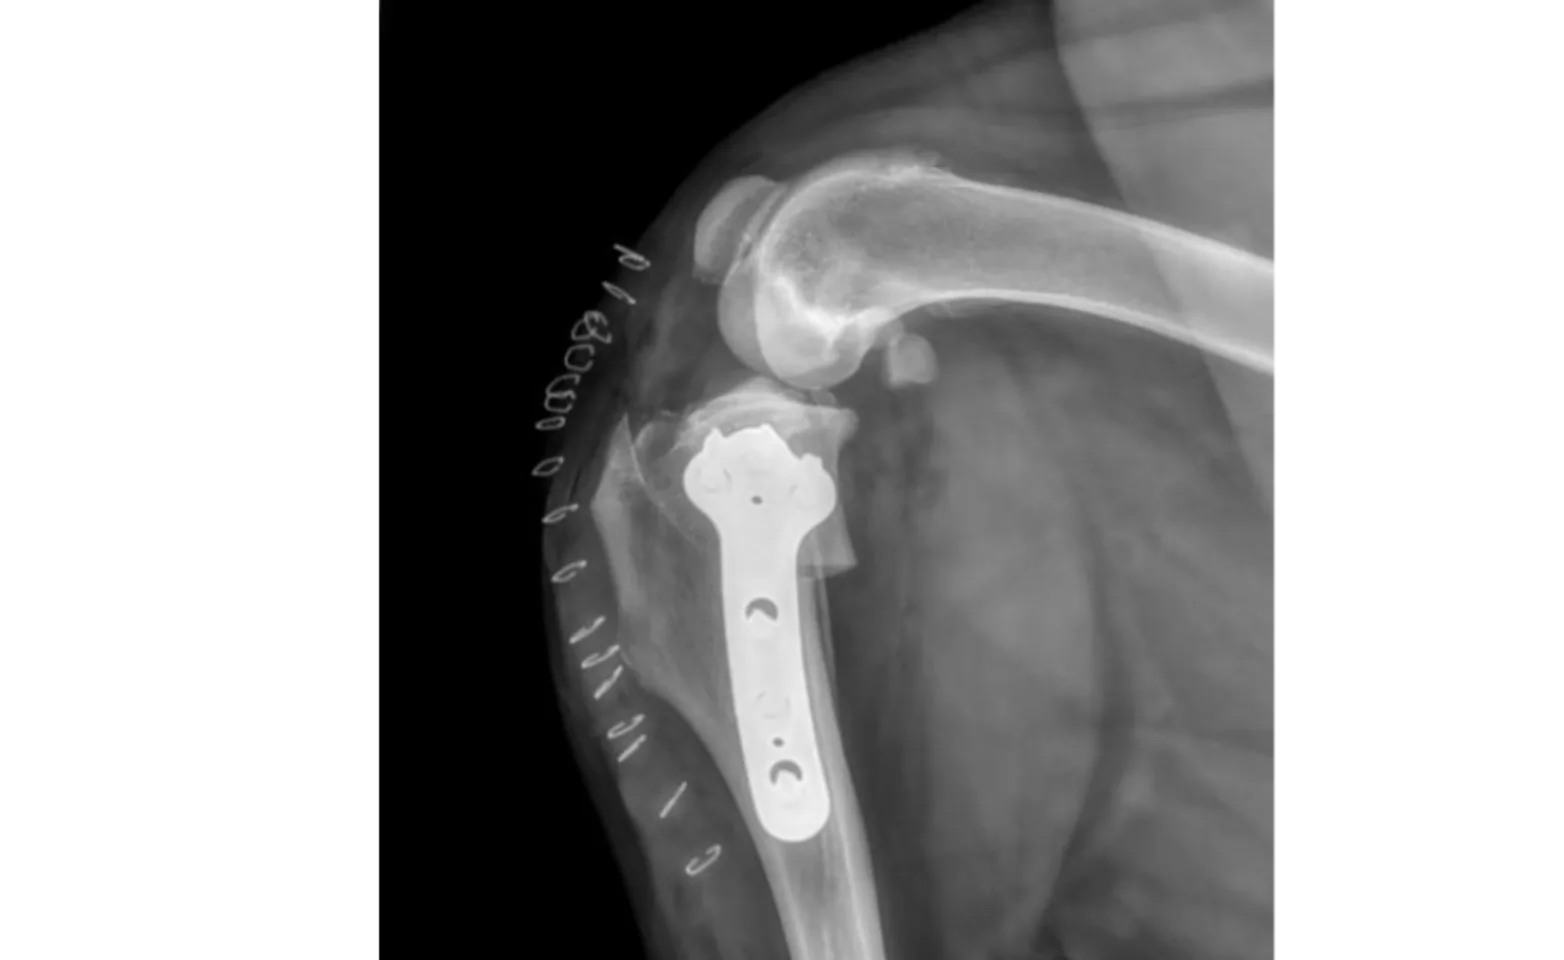

One of the most frequent orthopedic conditions Dr. Dorian treats is the rupture of the cranial cruciate ligament (CCL/ACL). The most common surgery performed for this problem is a TPLO (tibial plateau leveling osteotomy). A special saw is used to cut the tibia (shin bone), this piece is rotated slightly and secured with a plate and screws. This procedure changes the physics of the knee, which allows your pet to walk much more comfortably even though the ligament is no longer present.

Another procedure can be performed for a CCL rupture, the Lateral Suture. This procedure is somewhat less invasive than the TPLO. However, it is usually reserved for smaller breed dogs (such as chihuahuas, yorkies, etc.), as medium/large/giant breed dogs tend to recover much better in the long run with a TPLO.